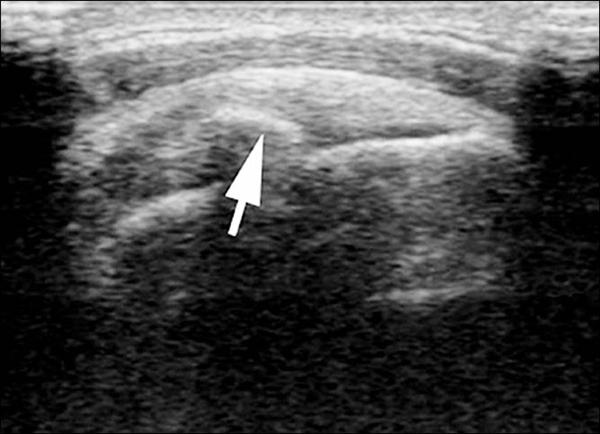

治療包括藥物、復健(物理治療)、震波治療、穿刺或抽吸、手術等。藥物治療的目的是止痛及消炎;復健除止痛外,還會強調肌肉、肌腱的訓練,及改善肩關節活動度;震波治療(圖3)類似泌尿科的體外碎石術,利用體外瞬間產生的巨大能量波,將鈣化物破壞,並促使周遭的組織產生新生血管,加速鈣化物的排除及身體修復。

穿刺或抽吸是在超音波的導引下,使用18至22號針頭多次穿刺或抽吸鈣化物,以加速鈣化物的排除(圖4)。